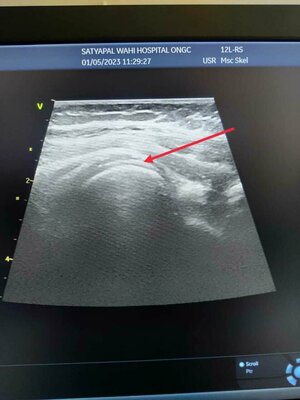

Shoulder Ultrasound - Easy and Inexpensive way of Diagnosing Shoulder Pain

A shoulder ultrasound is a non-invasive, painless imaging technique that uses high-frequency sound waves to produce images of the internal st...